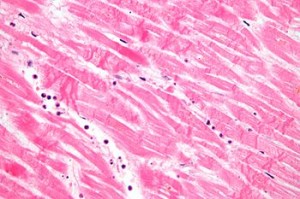

Histopathology

CBI offers histology and pathology, incuding immunohistochemistry, plastics, devices and histomorphometry in both a GLP and nonGLP environment for studies generated within CBI as well as from animals from field and academic studies. We welcome tissues from both companion animals and large farm or exotic animals.